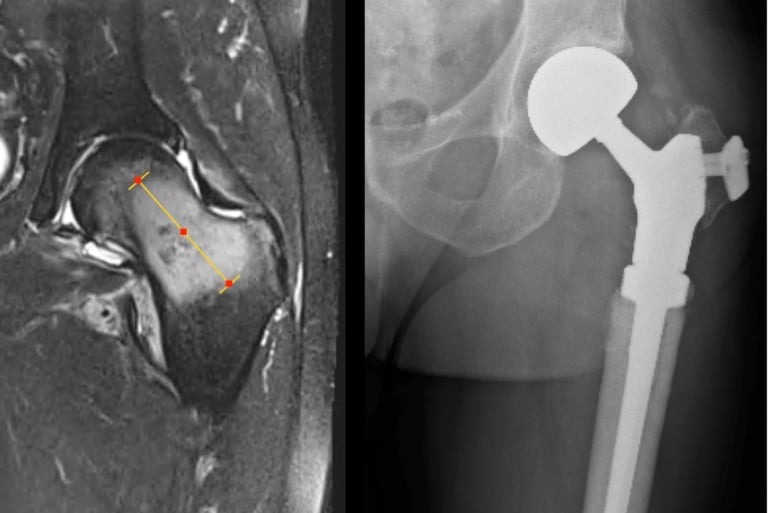

Management of these tumours can be very complex and Mr Pang is one of a few surgeons in Melbourne who has extensive experience in the surgical management of bone and soft tissue tumours / sarcomas. Management often include collaboration with other specialists of with similar interests (plastics, spinal and thoracic surgeons), complex resections such as the pelvis, utilisation of tumour / megaprosthesis and employing advanced computer navigation techniques to achieve precision tumour surgery.